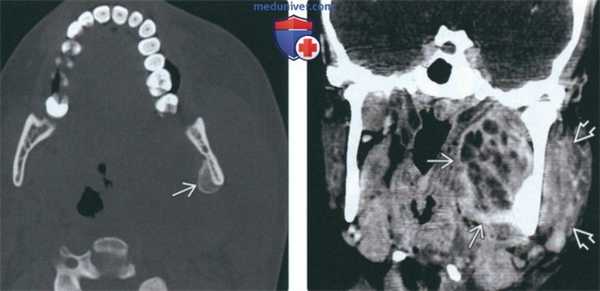

(Слева) На аксиальной КТ в костном окне у этого же пациента определяется периостальная реакция, характерная для остеомиелита нижней челюсти.

(Справа) На корональной КТ с КУ у этого же пациента определяется многокамерный абсцесс внутреннего жевательного пространства в сочетании с отеком и утолщением жевательной мышцы в наружном жевательном пространстве.

(Слева) На аксиальной КТ с КУ определяется абсцесс внутреннего жевательного пространства слева с вовлечением нижнего края медиальной крыловидной мышцы и воспалением жевательной мышцы. Этот пациент 22 лет с инфекцией моляра, не отвечающей на антибиотикотерапию, предъявляет жалобы на боль, отек и тризм.

(Справа) На аксиальной КТ с КУ у этого же пациента определяется распространение абсцесса книзу в левое поднижнечелюстное пространство. Также наблюдается реактивная лимфаденопатия II уровня.